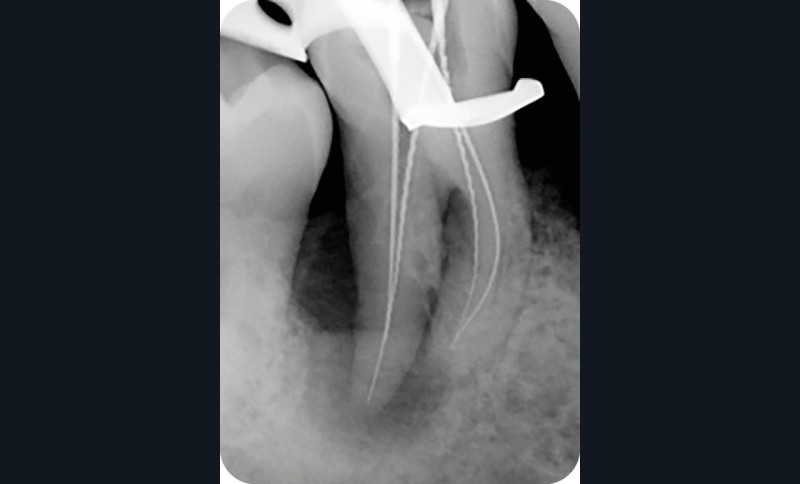

Radiographie per-opératoire |

2. Exemple de prise en charge d’une lésion endo-parodontale sans atteinte de l’intégrité radiculaire, chez un patient atteint de parodontite, de grade 3 (poche parodontale profonde sur plus d’une surface dentaire). Le traitement endodontique est réalisé dans un premier temps. Après réévaluation à 6 mois, une contention a été placée et une thérapeutique parodontale complémentaire a pu être réalisée (surfaçage et mise en place de matériaux de comblement). La maintenance parodontale est effectuée régulièrement afin de maintenir le résultat obtenu.